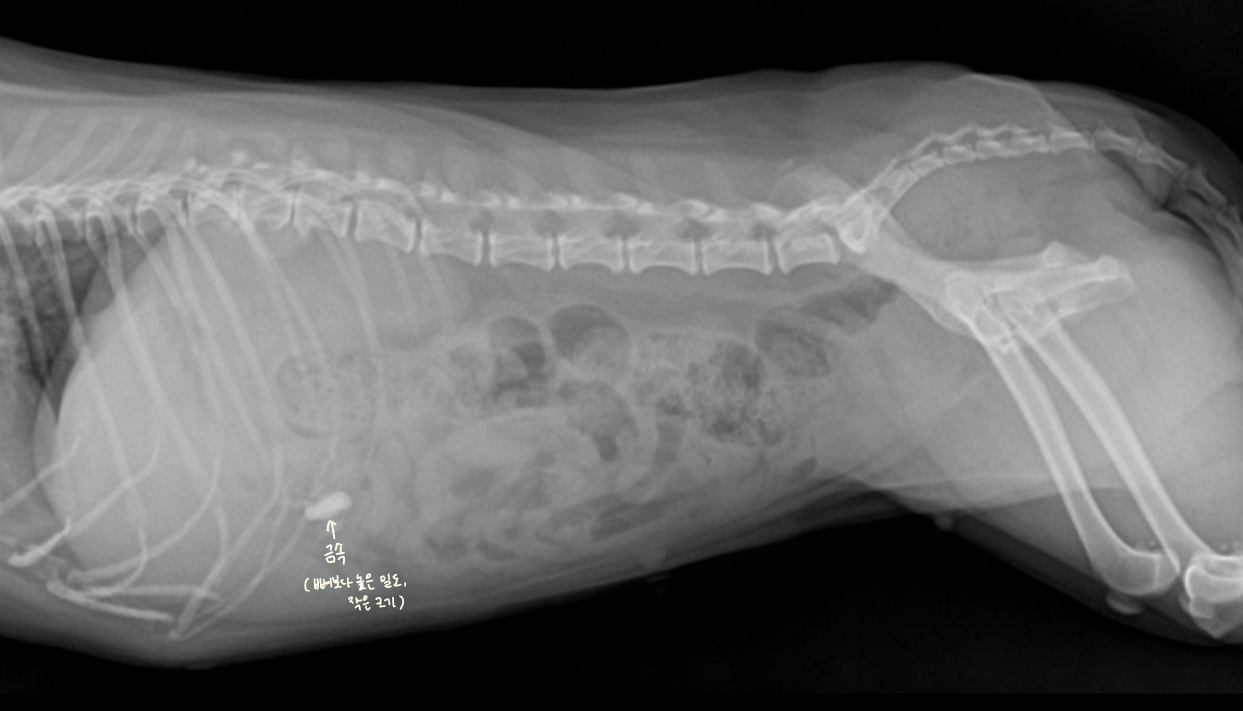

Anatomy (๋ณต๊ฐ ์ฅ๊ธฐ์ ์์น)

| Lateral |

|---|

| - stomach : ๊ฐ ์๋ gas๊ฐ ์ฐจ ์๋ ๊ตฌ์กฐ (์ฐจ ์๋ ๊ฑด ๋ค๋ฅผ ์ ์์) - duodenum : ์์ ๊ฐ์ด๋ฐ์์ ๋ป์ด๋๊ฐ - cecum : ์ฐ์ธก, ์ฌ์ฅ ์ฃผ๋ณ, gas๊ฐ ์ฐจ ์๋ ์ํ์ฑ ๊ตฌ์กฐ. (์์ ๋ฑ์ผ๋ก ์์น ๋ณํ ์ ์์) |